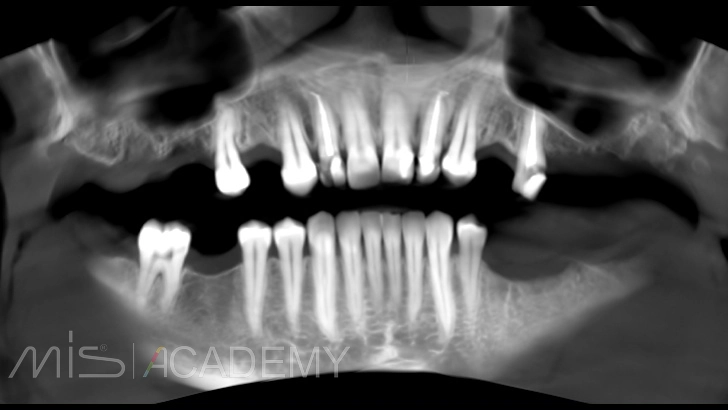

— На первом этапе было установлено три имплантата в области 2.4, 2.6 (закрытый синус-лифтинг) и 2.7 (птеригоидная установка).

— Через 3 месяца было обнаружено отторжение имплантата в области 2.6, потеря костной ткани в области шейки. Для устранения данного осложнения, во время удаления имплантата 2.6 был фиксирован костный блок, взятый из бугра верхней челюсти справа.

— Одномоментная переустановка имплантата в области 2.6.

— Через 2 месяца обратился к нам с удаленным зубом 2.5, что меняет тактику дальнейшего лечения.